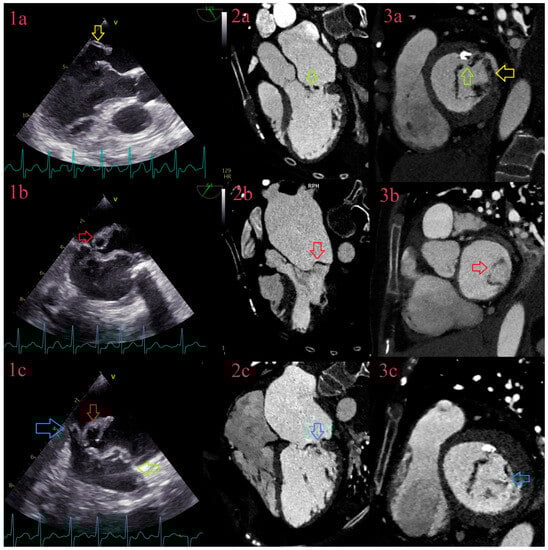

3.6. Abscesses

3.7. Pseudoaneurysms

3.8. Fistulas